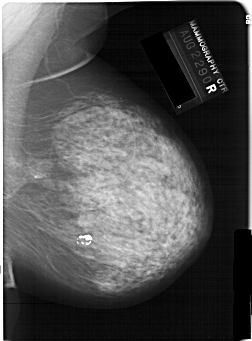

A_1146_1.RIGHT_MLO

RIGHT_MLO LINES 6466 PIXELS_PER_LINE 4771 BITS_PER_PIXEL 12 RESOLUTION 43.5 NON_OVERLAY